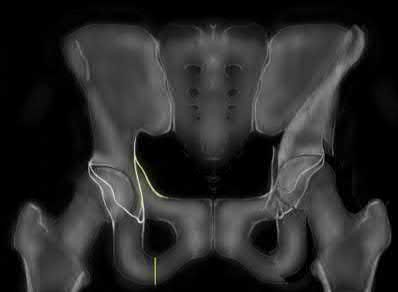

A poly-trauma patient presents hemodynamically unstable with an anteroposterior compression (APC-III) pelvic ring injury. A circumferential pelvic binder is requested to reduce pelvic volume and control hemorrhage. To be anatomically effective, the binder must be centered precisely over which of the following landmarks?

For optimal mechanical advantage and effective reduction of an 'open book' pelvic fracture (APC type), a pelvic binder must be applied directly over the greater trochanters of the femurs. Applying it higher, such as over the iliac crests, is a common error that fails to adequately close the pelvic ring and can paradoxically open the true pelvis.